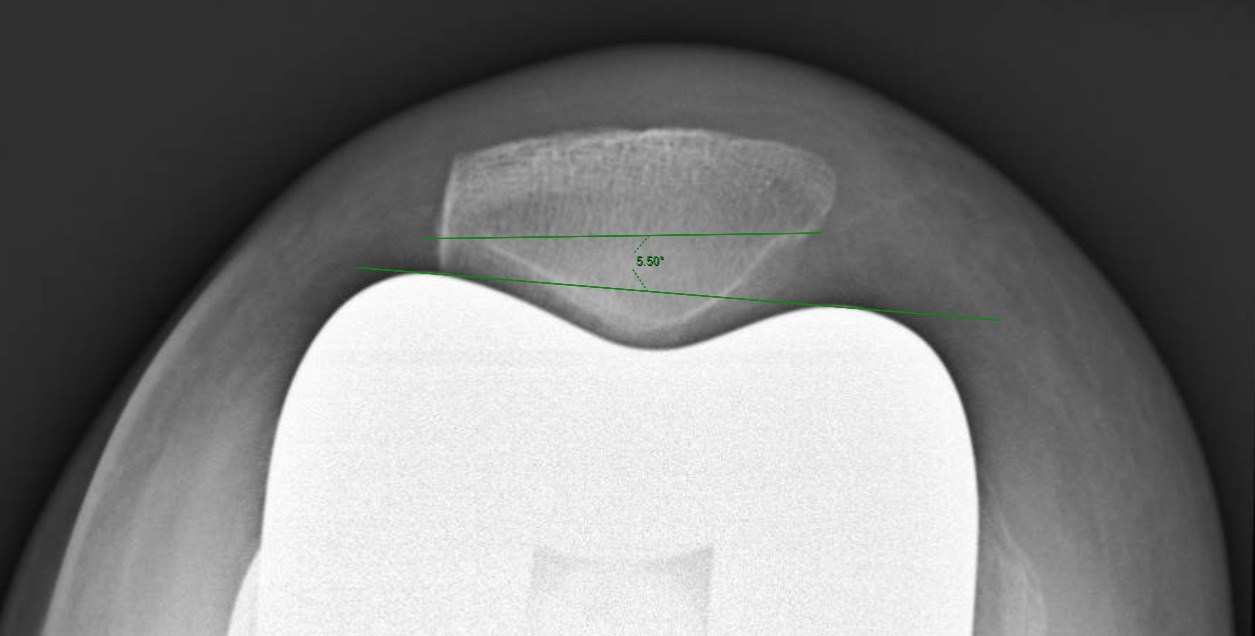

Measurements were performed by one rater following extensive training from the senior author using a standardized measurement protocol. The rater was blinded to the use of robotics when measurements were made. Assessment of postoperative merchant view radiographs on digital imaging software according to the method of Gomes et al. was conducted (Gomes, Bechtold, and Gustilo 1988). The angle between the resected surface of the patella and a line tangent to the anterior condylar axis of the femoral component was measured and recorded (Figures 1-4). The patellar tilt was recorded as positive when the tilt was lateral and was recorded as negative when the tilt was medial. The absolute value of the patellar tilt was used during data analysis as a neutral of 0° was considered the goal for patellar tilt during surgery, and both increasing lateral and medial tilt away from neutral were considered as increasingly imperfect. The percentage of outliers where the patellar tilt exceeded 3 degrees off neutral was also calculated for each group.